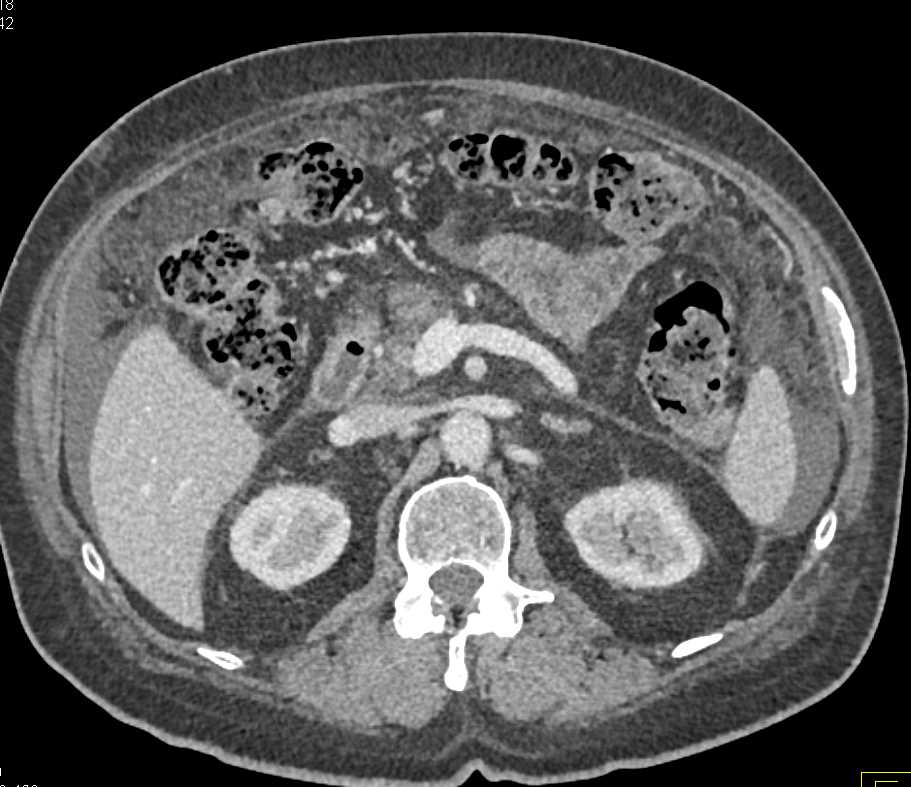

Gastric Cancer with Carcinomatosis